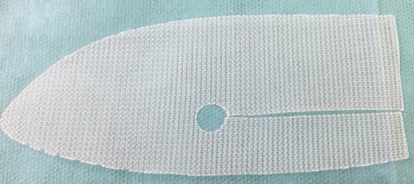

Chirurgie

Filet

- Au niveau de l’orifice inguinal profond

- Trou pour laisser le cordon spermatique

- Masque tout en echo (bande hyperechogène et cône d’ombre)

- Complications

- Récidive en bord de plaque

- Fréquemment un aspect ondulé (banal)

- Retraction nodulaire: Pathologique (fait des douleurs)

- Lymphocèle du corodn

- Hématome du cordon

- Varicocèles du cordon

Récidive en bord de filet

Filet qui masque tout

Aspect ondulé

Retraction nodulaire pathologique

Filet au CT